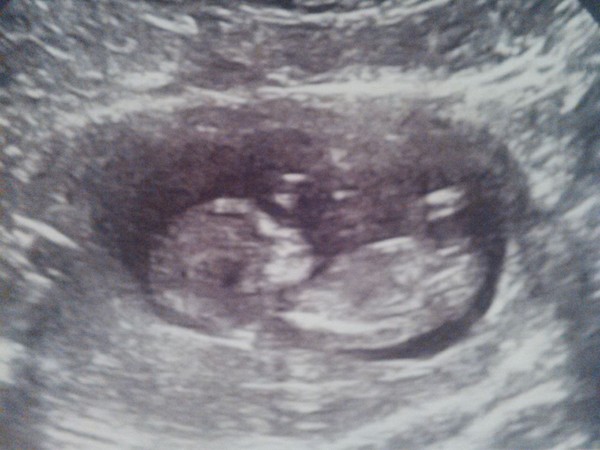

Aww scan pics galore. Lovely :) so cute!

Lovely news tilly and a great scan pic. Everyone has such clear images, I hope ours is as good. 11 sleeps to go til our 12w one. Not that I'm counting...

Aww loving the scan pics :) will upload mine if i work out how! Are any of you looking into nub theory? From that mine looks like a boy but guess will see

Lovely scan pics, going to try to put mine. I would love to get an early gender scan the one is not I'm 22 weeks I am far too impatient Smile

What beautiful scan photos. I'm counting the days until mine like a child waiting for Christmas - only 6 more sleeps to go - hehehe!

Up with insomnia over work related stress, but OMG at all these gorgeous scan pictures! Completely made my night. Grin

Lovely waking up to all these scan pictures, congratulations everyone. I'm also on count down, only four more sleeps. Can't wait.